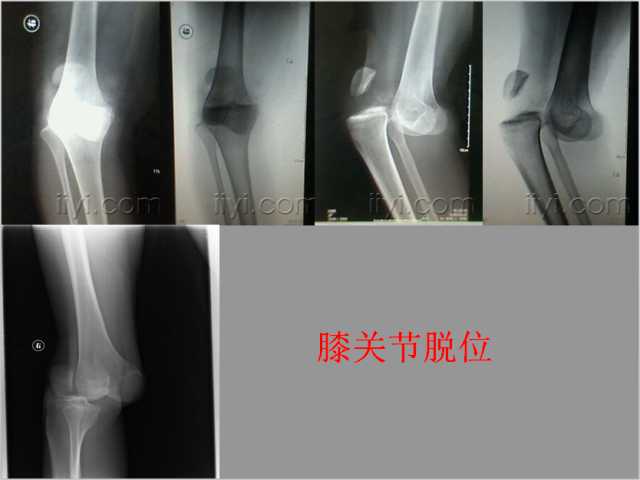

关节脱位篇

02

定义:关节脱位是暴力、关节感染、附近软组织挛缩或先天骨发育障碍造成的关节对位关系部分或完全脱离,即为半脱位或脱位。临床上以创伤性脱位*常见。